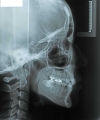

日本矯正歯科学会専門医課題症例(第4症例)

カテゴリー:ClassⅡ division 2 malocclusion (Overbite 5mm以上; 抜歯症例)

出題基準:大臼歯関係がclass Ⅱで、上顎中切歯1本を含む2本以上が舌側傾斜(U1-SN 90度以下)、犬歯関係もclass Ⅱであること。ただし、日本人では症例が少ないことを考慮して、U1-SN 100度以下のclass Ⅱ過蓋咬合も認める。抜歯・非抜歯は問わない。

出題の意味:このケースの条件は一般の人には理解しにくいところがある。通常出っ歯というと上の前歯が外に向かっていることを想像するのが普通であるが、U1-SNが90度以下というのは、上の前歯は内側に傾いていることを示している。なんで??。つまりこれは骨格性上顎前突と考えられるもので、上顎が歯並びごと全体が前へ出ていて、それだと上下の前歯があまりにも離れてしまうため、上の前歯が内側に倒れて下の前歯と何とか接触しようとしている状態と考えられる。

しかし、出題基準にも書いてあるように、このケースは欧米の白人によく見られるケースで、東洋人にはきわめて稀である。そこで類似ケースとして過蓋咬合(かがいこうごう)のケースを代替えとして認めるという配慮をしている。過蓋咬合とは非常に強く深く咬んでいる状態を言う。Overbiteとは前歯の垂直的な重なり具合を示す数値で、5mm以上だと上の前歯が下の前歯をほとんど覆い尽くしている感じになるので、前から見ると下の前歯はほとんど見えない状態になる。こういう状態が典型的な過蓋咬合である。典型的なclassⅡ,division 2のケースは過蓋咬合を合併している。